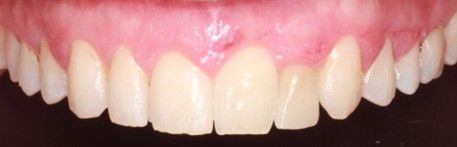

El objetivo del presente caso clínico es describir la colocación de un implante monobloque de circona para reponer un incisivo lateral superior izquierdo en un paciente de 34 años de edad, para la posterior realización de una corona implantosoportada monolítica de circona.

La rehabilitación mediante implantes de circona para el tratamiento de agenesias congénitas en incisivos laterales superiores, es una opción válida y efectiva, obteniendo resultados óptimos a nivel estético y funcional.

El objetivo del presente caso clínico es describir la colocación de un implante de circona para reponer un incisivo lateral superior izquierdo en un paciente de 34 años de edad, para la posterior realización de una corona implantosoportada monolítica de circona.